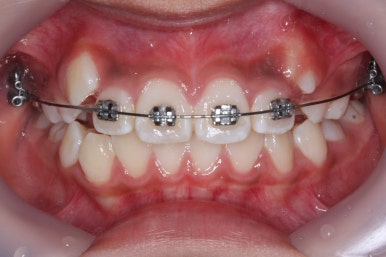

첫 장치 부착한 모습입니다.

아직 유치가 몇 개 남아있기에 장치가 전체적으로 부착되지 않습니다. 우선 앞니 4개만 먼저 치열을 맞추고 위쪽 어금니는 후방 이동을 해주면서 교합을 맞추며 덧니가 내려올 공간을 확보합니다.

연산동덧니교정 키다리아저씨치과에서는 메탈 장치를 사용했습니다.

많이 사용 되는 클리피씨 장치 등의 세라믹 보다는 아이가 양치하기 쉬운 부피가 작고 비용도 덤으로 낮은 메탈장치를 사용했습니다.